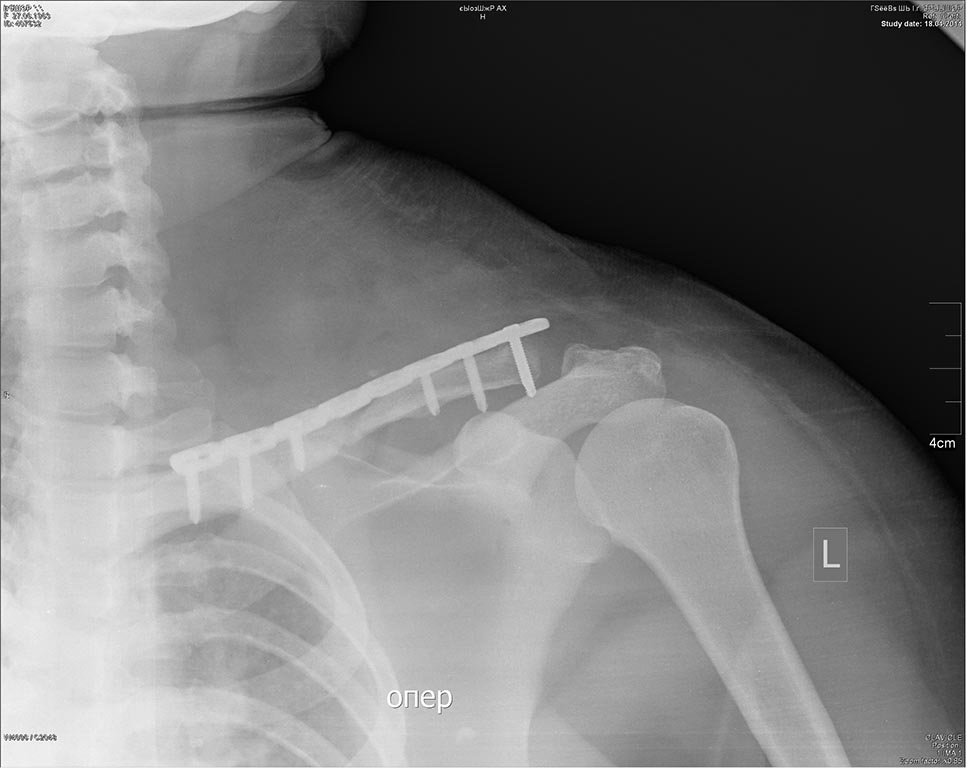

Большое спасибо всем! Больную вчера прооперировал (только ключицу пластиной LCP).

Интраоперационно: 1)ключично-клювовидная связка состоятельна. 2) после мобилизации отломков и восстановления оси прилагал усилия для устранения диастаза(обычно наоборот). 3)по ощущениям лопатка "болталась".

На сегодня активно отводит плечо до (+-)70гр. Боли умеренные только в области послеоперационной раны. Будем смотреть дальше...

Снимок до... и после.